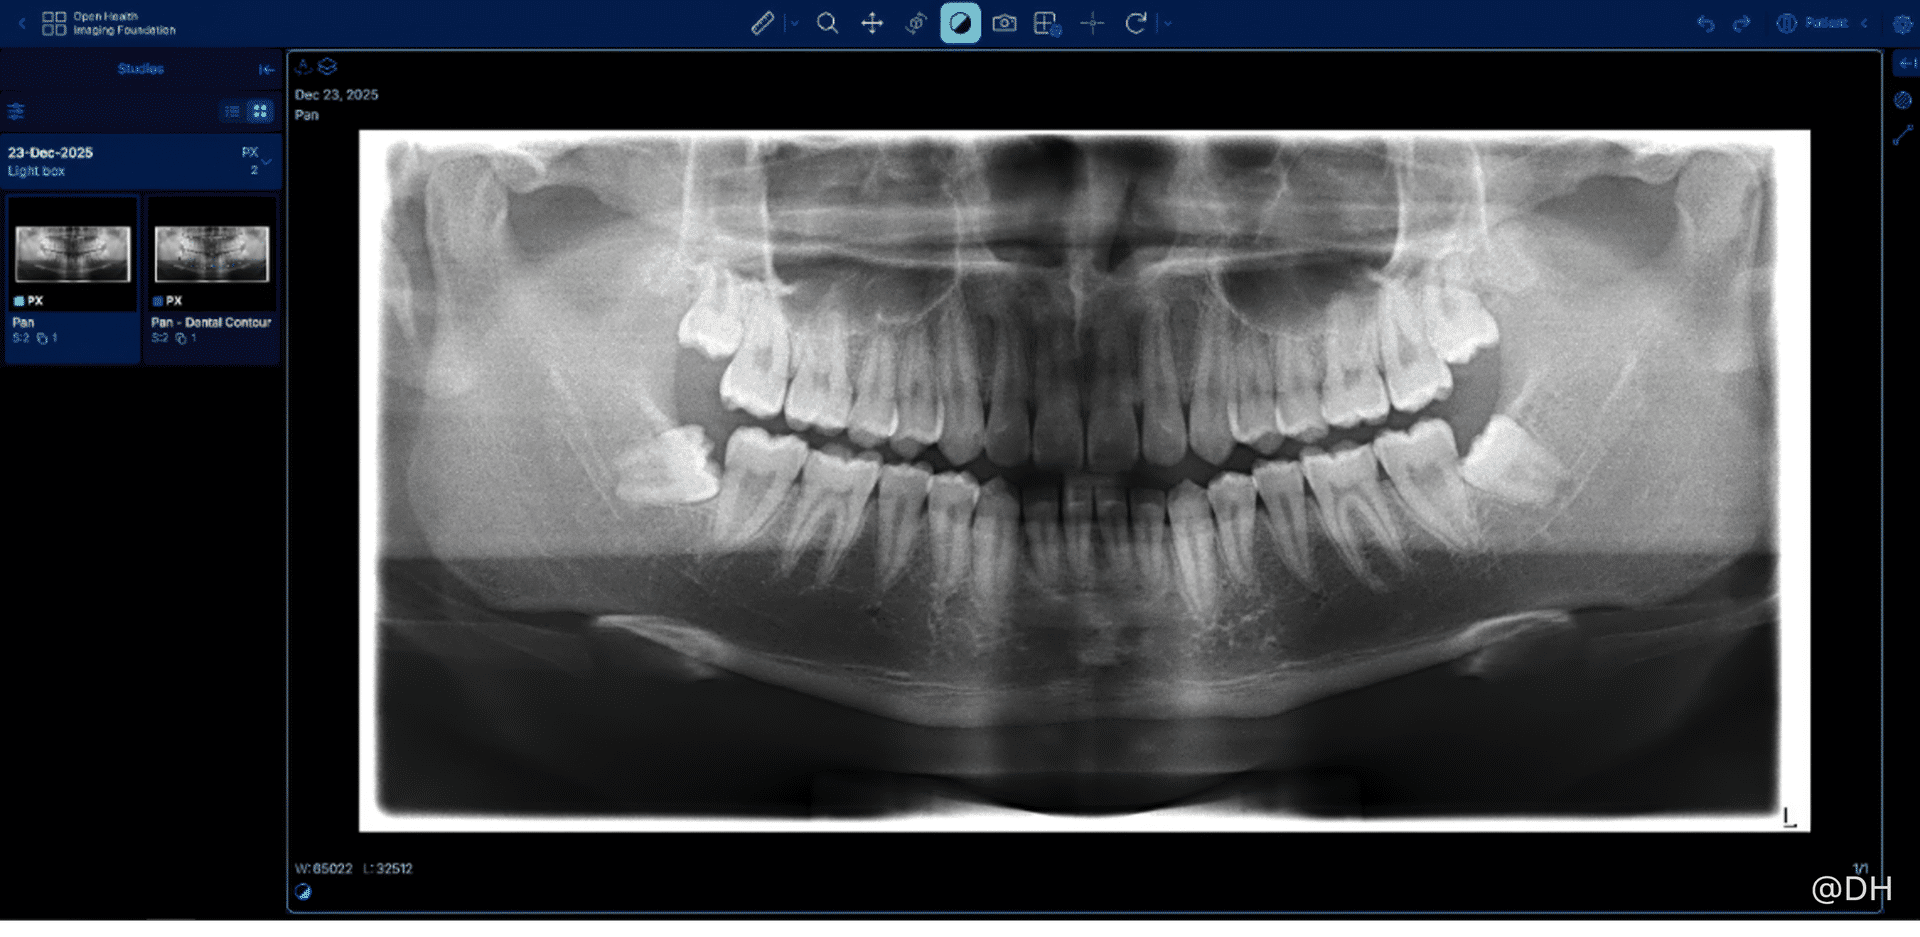

图片说明﹕原始的牙科全景X光影像

卫生署已采用电子临床资讯管理系统多年,但工作流程上仍依靠人手输入病人的临床牙齿检查资料,每个个案平均需时10分钟。为减轻牙医与助理的临床文书负担,优化服务流程,卫生署去年开展名为“人工智能辅助牙科图表及解读X光影像系统”的概念验证项目。项目利用先进的半监督对比学习方法,以AI解读牙科X光影像,AI先自动侦测并分割牙齿影像,根据空间与形态特征为每伙牙齿标注国际牙科联盟(FDI)牙齿编号;项目同时验证了将影像分析转化为结构化资料,自动生成牙科图表,并与临床管理系统整合的潜力。

为期约六个月的概念验证项目已于今年一月成功完成,项目所发展出的解读牙科X光影像的AI原型,临床案例灵敏度高达96%,牙齿级精确度高达94%,效果令人满意。